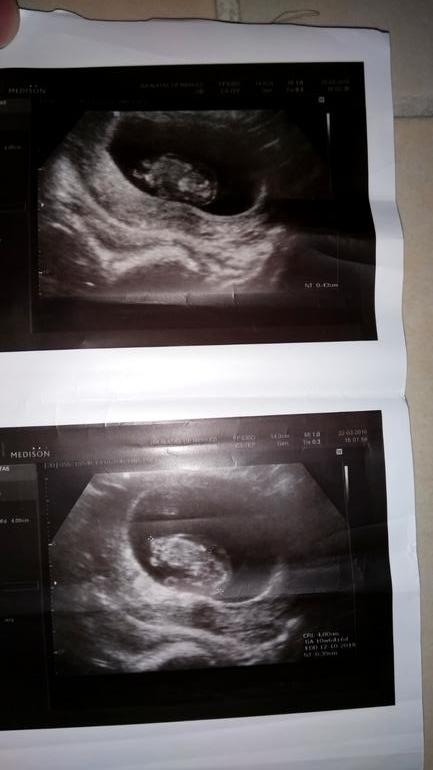

девочки,пошла на узи сказали подозрение на дауна ,но не точный диагноз